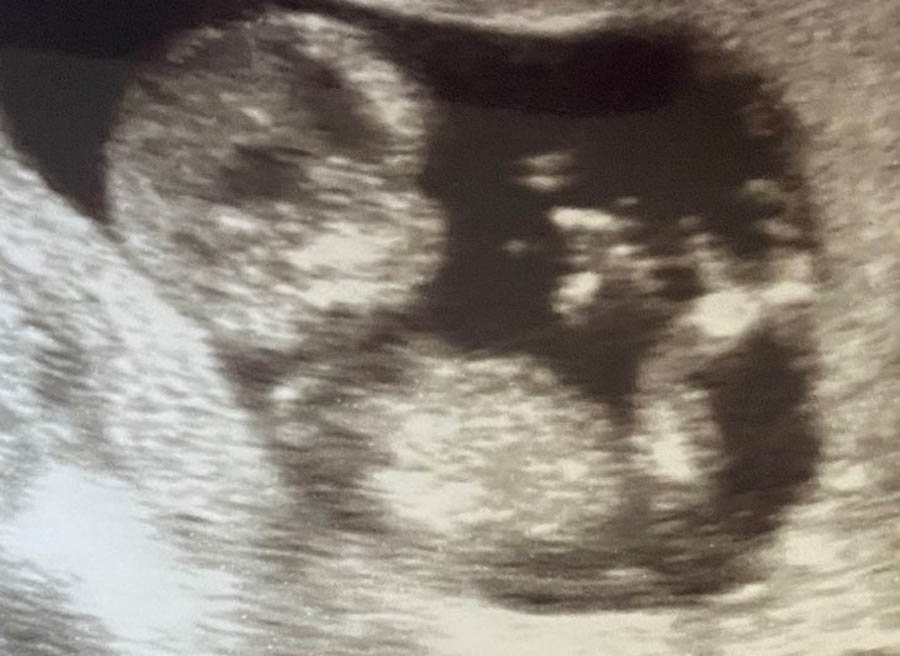

Christa serves as the Senior Director of Medical Impact for Heartbeat International, offering support and training to medical clinic affiliates throughout the world and overseeing the Abortion Pill Rescue Network. The APRN is a global initiative operating 24 hours a day, staffed with a dedicated nursing team and a network of more than 1,000 medical professionals as well as clinics, hospitals, and pharmacies. Through the network, thousands of lives have been saved in 93 different countries and all states in the U.S. Christa has served in leadership in Pregnancy Help Organizations for over twenty years in Indiana and Michigan --as Nursing Director, Executive Director, Marketing Director, Director of Internet Communications, and as Director of Resource Development. She led the opening of new pregnancy help medical clinics in seven other states including staff training, building preparation, and board development. Christa has empowered thousands to navigate challenging circumstances and choose life for their children. Christa is married and has five children and nine grandchildren. Christa's advocacy for women and families worldwide has made a profound impact on women's health and the sanctity of life.